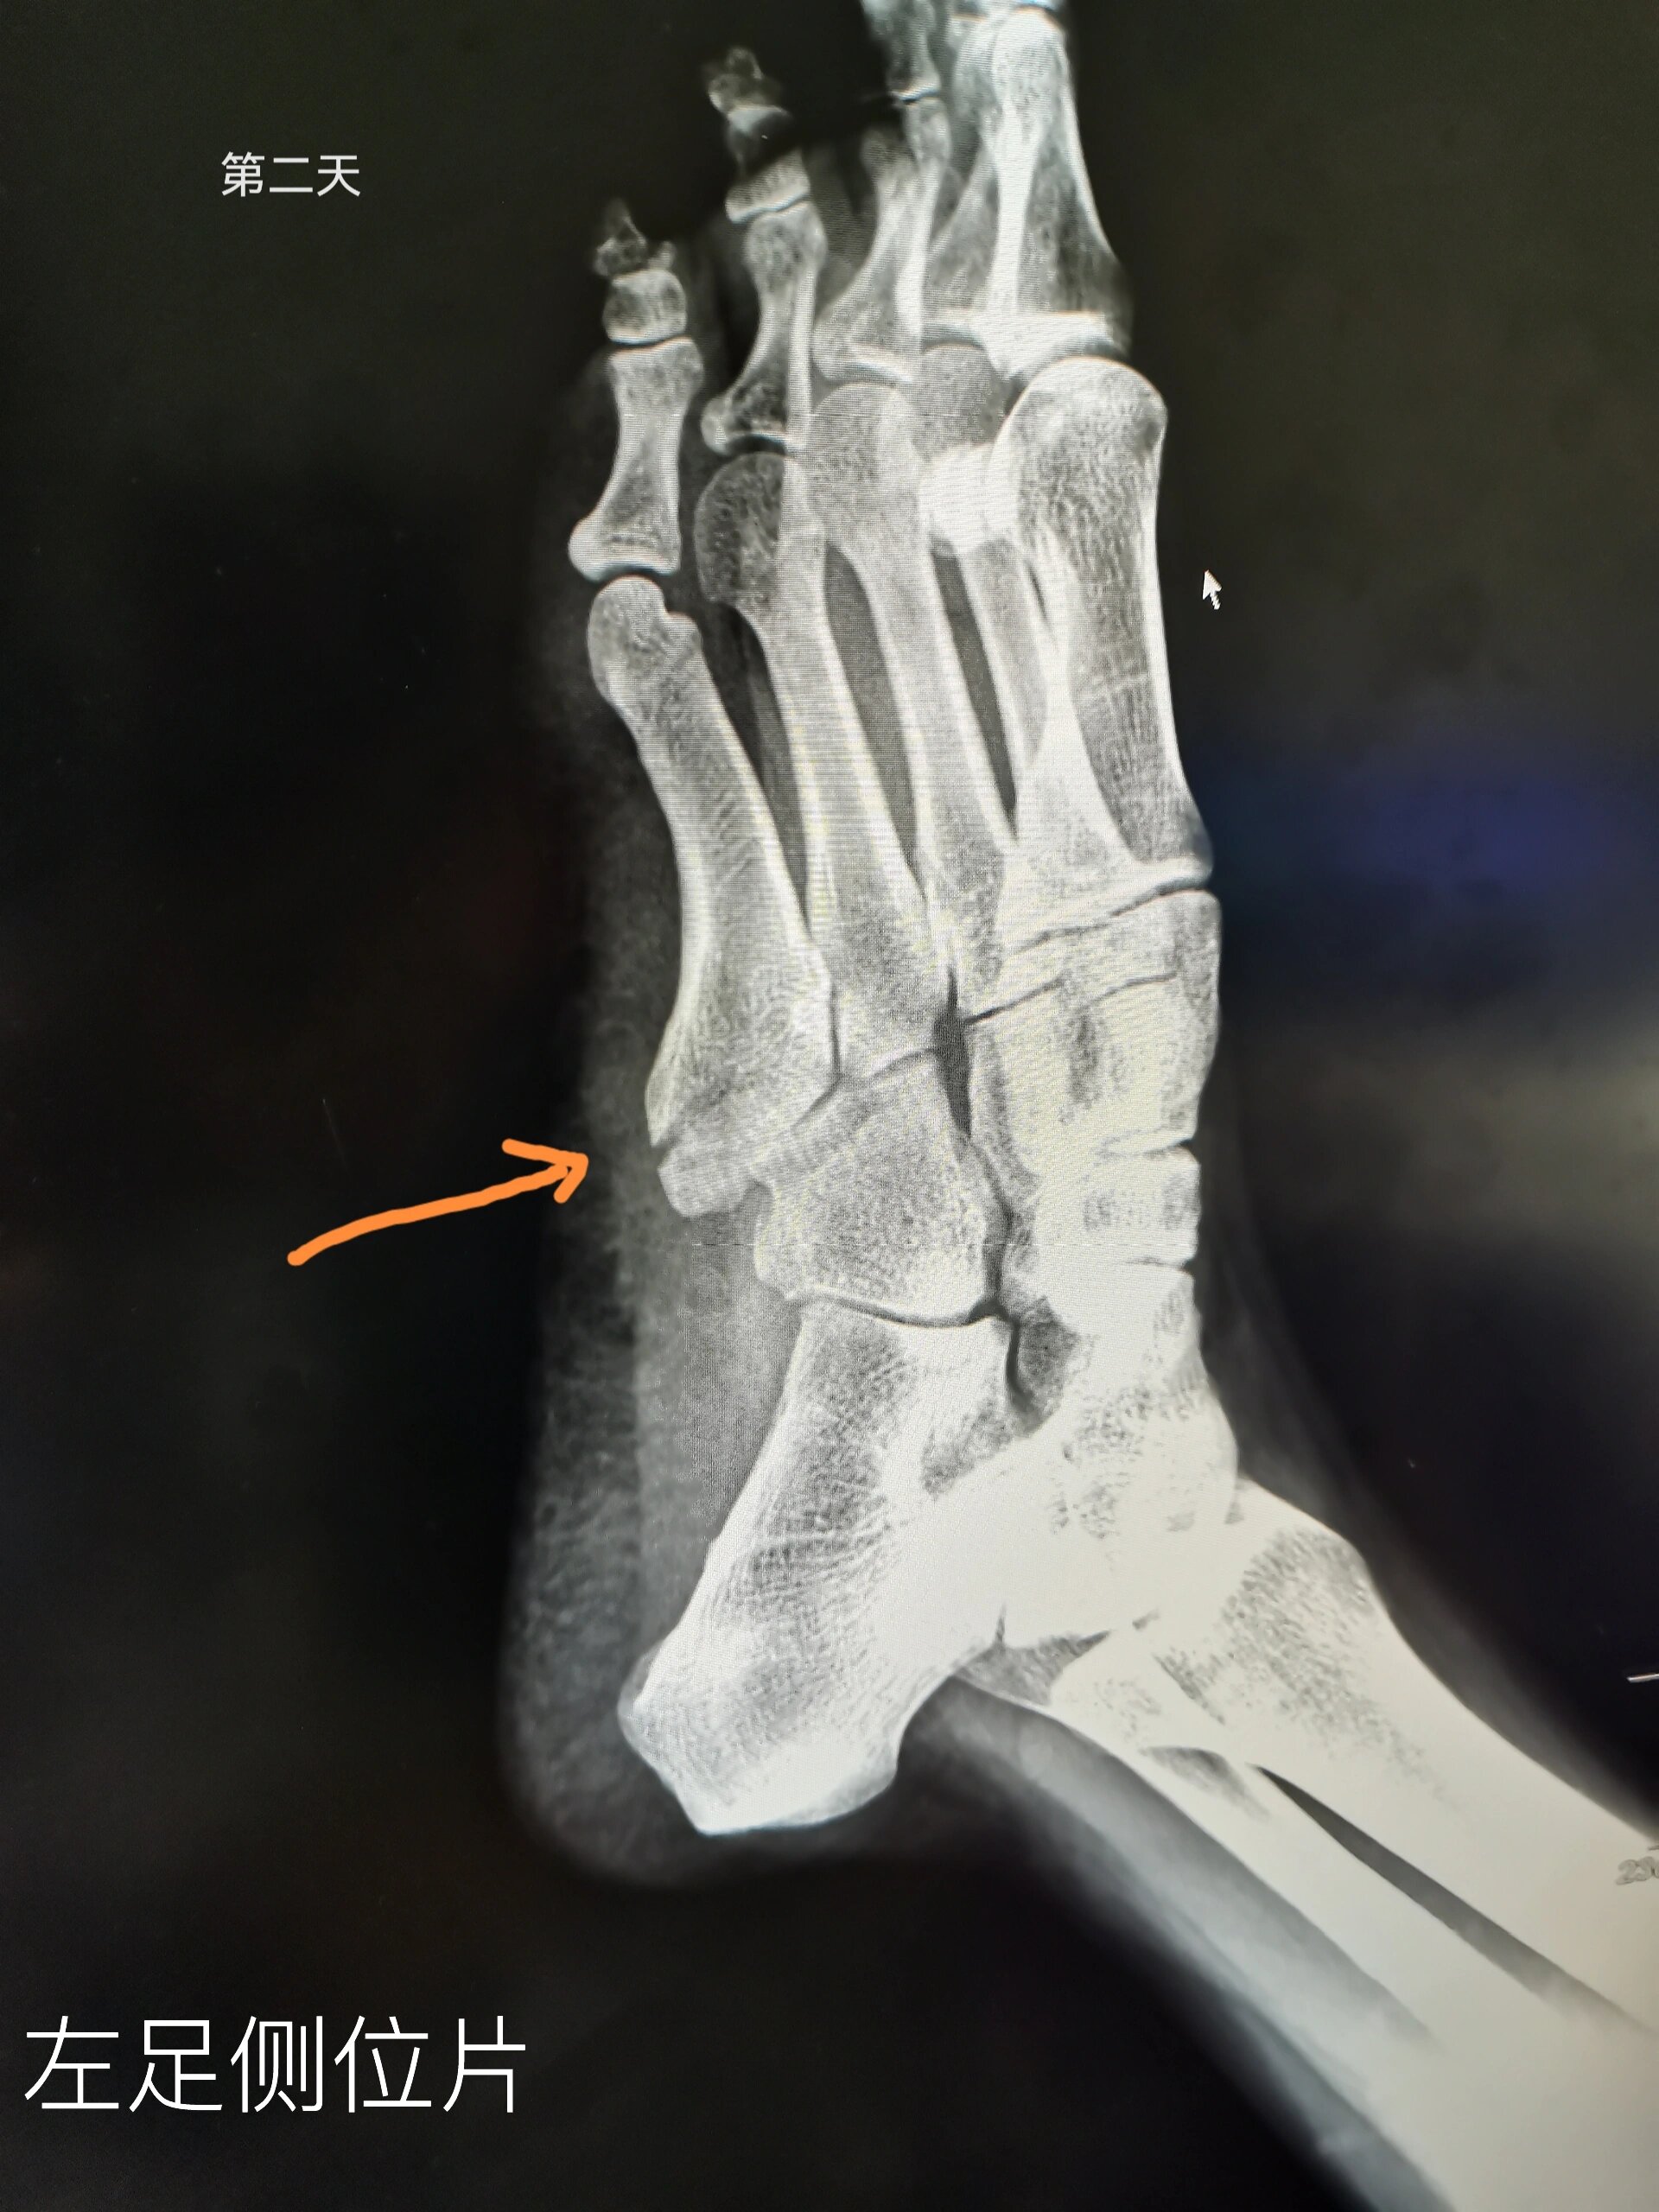

左足第五跖骨基底部撕脱性骨折 8月22号下楼梯扭脚

足部侧位.jpg